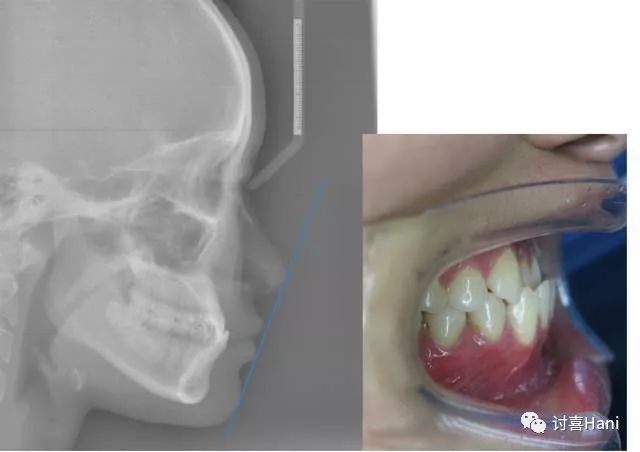

牙齿反颌:上下牙的错合度较小,从外观上没有明显的凹面感,甚至看不太出来。

▲来自牙医潘超的案例